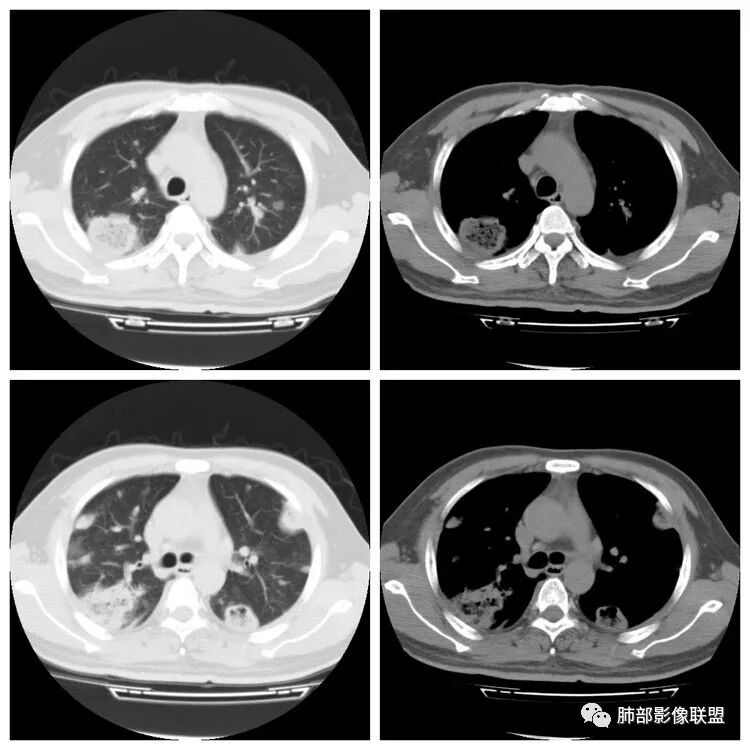

胸 CT

南边:胸膜下,类圆形,边界清,内有坏死,典型的反晕征,支气管壁增厚不明显,支持血道来源脓毒栓子所致梗死、感染

血道来源没问题

左下叶大片类似病灶

治疗后改变

肺克的影像表现(唐绍宏总结):分布:单侧上叶病变,以右肺上叶多见;患者长期卧床则双脚下肺后基底段分布(国外下肺多见,可能与平均寿命长,卧床及住托老机构多有关) ;如多叶段病变,则以肺上叶后段或下叶后基底段为最明显形态:气管壁增厚、磨玻璃、小叶实变、节段实变、大叶实变,坏死小空洞(直径小于2cm) ,少量胸腔积液50%、脓胸20%特点:早期气管壁增厚较明显、广泛,越靠近病灶越明显,越靠近肺门越明显,见于实变病灶外,偶尔见于磨玻璃影内(支气管通气征) ;未经抗生素治疗,实变病灶内无支气管通气征;早期即可出现坏死,无论坏死还是空洞,绝大多数直径小于2cm (可能与此菌有厚夹膜有关,参考隐球菌)